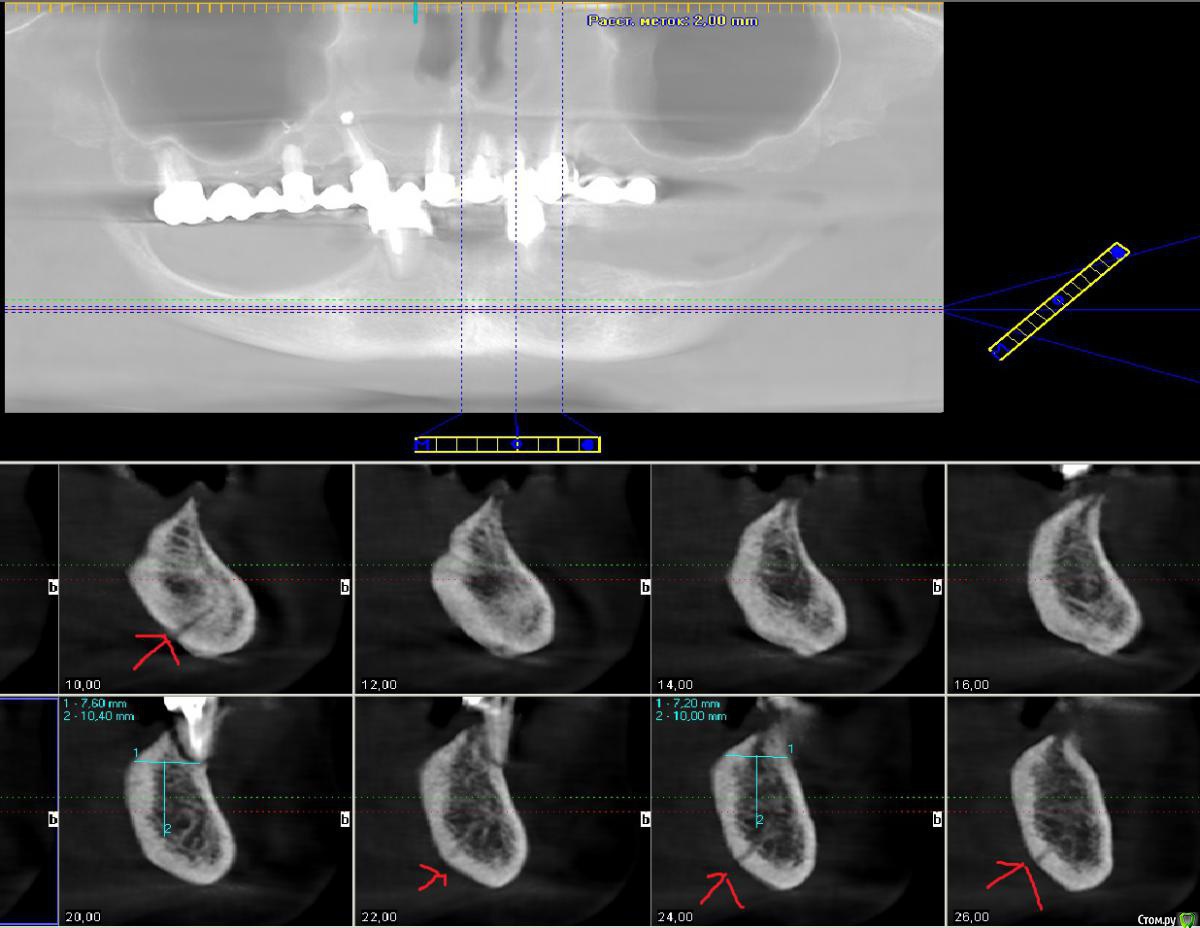

Rash163 Опубликовано 14 мая, 2015 Поделиться Опубликовано 14 мая, 2015 http://s019.radikal.ru/i601/1505/3e/3036b494e3f6.jpghttps://youtu.be/3EoYQZpMS48Показалось? Или действительно на кт в 43 и 33 входы сосудов? Ссылка на комментарий

kriokov Опубликовано 14 мая, 2015 Поделиться Опубликовано 14 мая, 2015 (изменено) Показалось? Или действительно на кт в 43 и 33 входы сосудов?похоже так но лучше просто скрины с кроссекциями' яснее будет Изменено 14 мая, 2015 пользователем kriokov Ссылка на комментарий

kriokov Опубликовано 15 мая, 2015 Поделиться Опубликовано 15 мая, 2015 не критично, все прям как в книгах. Один сосуд низко, второй повыше. Но оба в центральной зоне, Вы же болт по центру симфиза не будите крутить. Канала нет, справа кость не очень плотная помоему. 1 Ссылка на комментарий